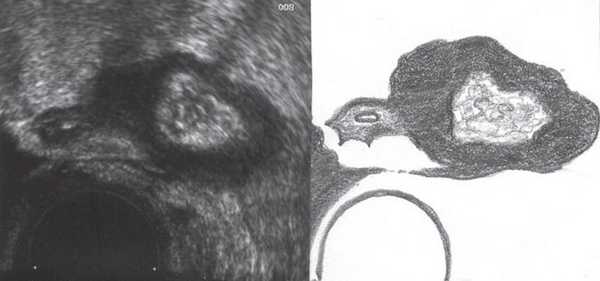

В то же время общедоступный относительно простой ультразвуковой метод также позволяет установить диагноз, при этом удается визуализировать дополнительную структуру округлой или овальной формы с четкими контурами рядом с желчным пузырем. Данное дополнительное образование визуализируется в различных позициях. Содержимое дивертикула варьирует от анэхогенного до неоднородного при наличии конкрементов в полости желчного пузыря. Дифференциальную диагностику проводят с аномалиями желчного пузыря (перетяжки, двойной желчный пузырь), с перфоративным холециститом с наличием затека в ложе желчного пузыря, с кистами печени.

Диаметр проксимальной части холедоха 0,3 см. Желчный пузырь типично расположен, размерами 7,5 х 2,2 см, с перегибами ближе к шейке и в теле (рис. 1). Контуры четкие, ровные. Стенка толщиной 0,2 см, эхогенность стенки повышена. Содержимое пузыря гомогенное.

Рис. 1. Эхограмма желчного пузыря до пищевой нагрузки.

В ложе ближе к шейке желчного пузыря, нечетко дифференцируясь от задней стенки, определяется жидкостная структура с тонкими стенками и однородным содержимым размерами 0,9 х 0,6 х 1,1 см (рис. 2), аваскулярная (рис. 3, 5), не меняющая размеров и формы после пищевой нагрузки (рис. 4). Соустье между описываемой структурой и задней стенкой пузыря визуализируется нечетко.

Рис. 2. Эхограмма дивертикула задней стенки желчного пузыря до пищевой нагрузки.